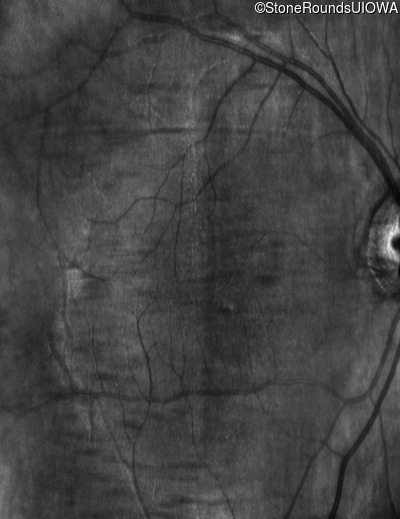

Infrared Fundus Photograph - Right - 10/160 sc

Exemplar

Infrared Fundus Photograph - Left - 10/200 sc